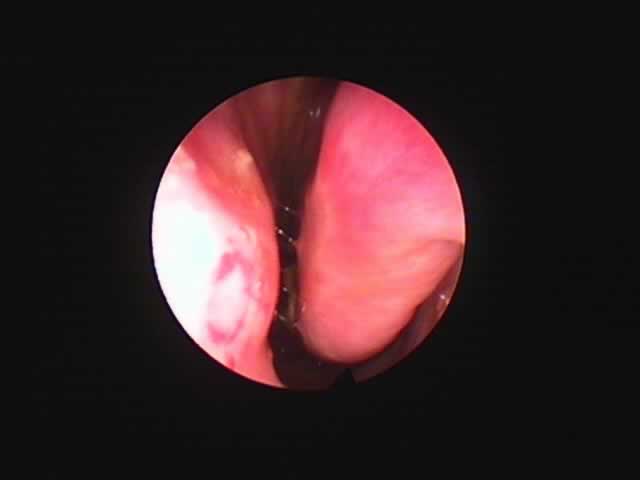

![]() |

右 |

左 |

| 術前 56歳 慢性肥厚性鼻炎 | コブレーション2ヶ月後 |

| いびきも消失。夜間の鼻閉が無くなり本人満足。 |